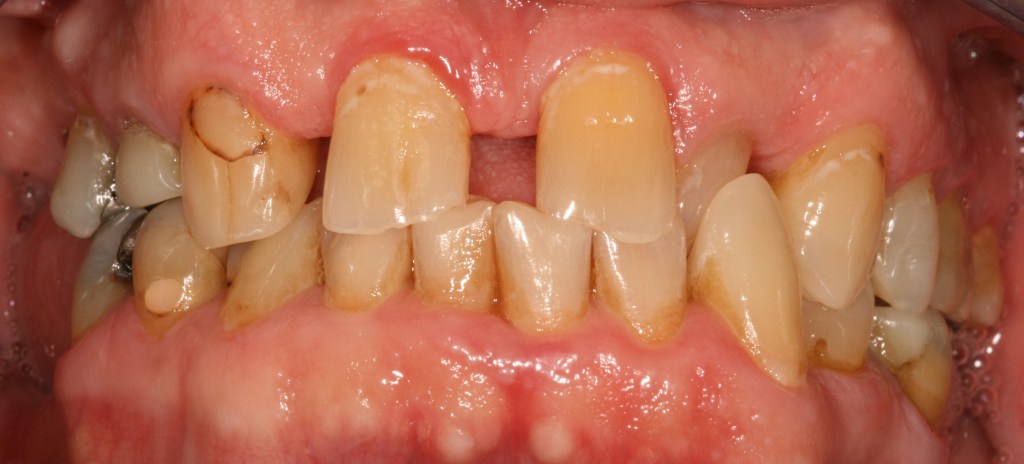

Funkcionális és esztétikai kezelés: harapás korrigálása a fogív kiegyenesítése, fogak közötti rések szűkítése, kereszt harapás megszüntetése az összes megmaradt fog koronázásával. A hiányzó hátsó fogak pótlása implantátumokon megtámasztott koronákkal.

Protetikai munka elkészülésének ideje: 10 munkanap

Koronák anyaga: fémkerámia

Fogszín: A1.